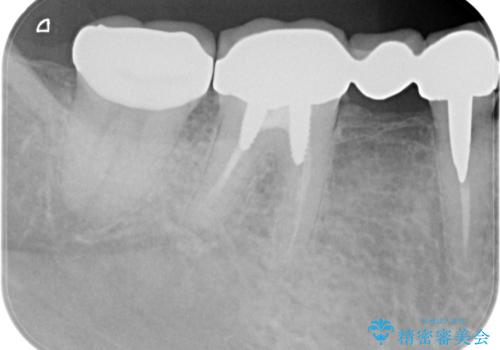

インレー下に再発した虫歯 セラミッククラウンによるやり替え

- 13.2万円(ジルコニアクラウン・仮歯)費用は治療当時の料金となります

再発した虫歯は小さくなかったものの、丁寧に虫歯をとることで神経を温存することができました。